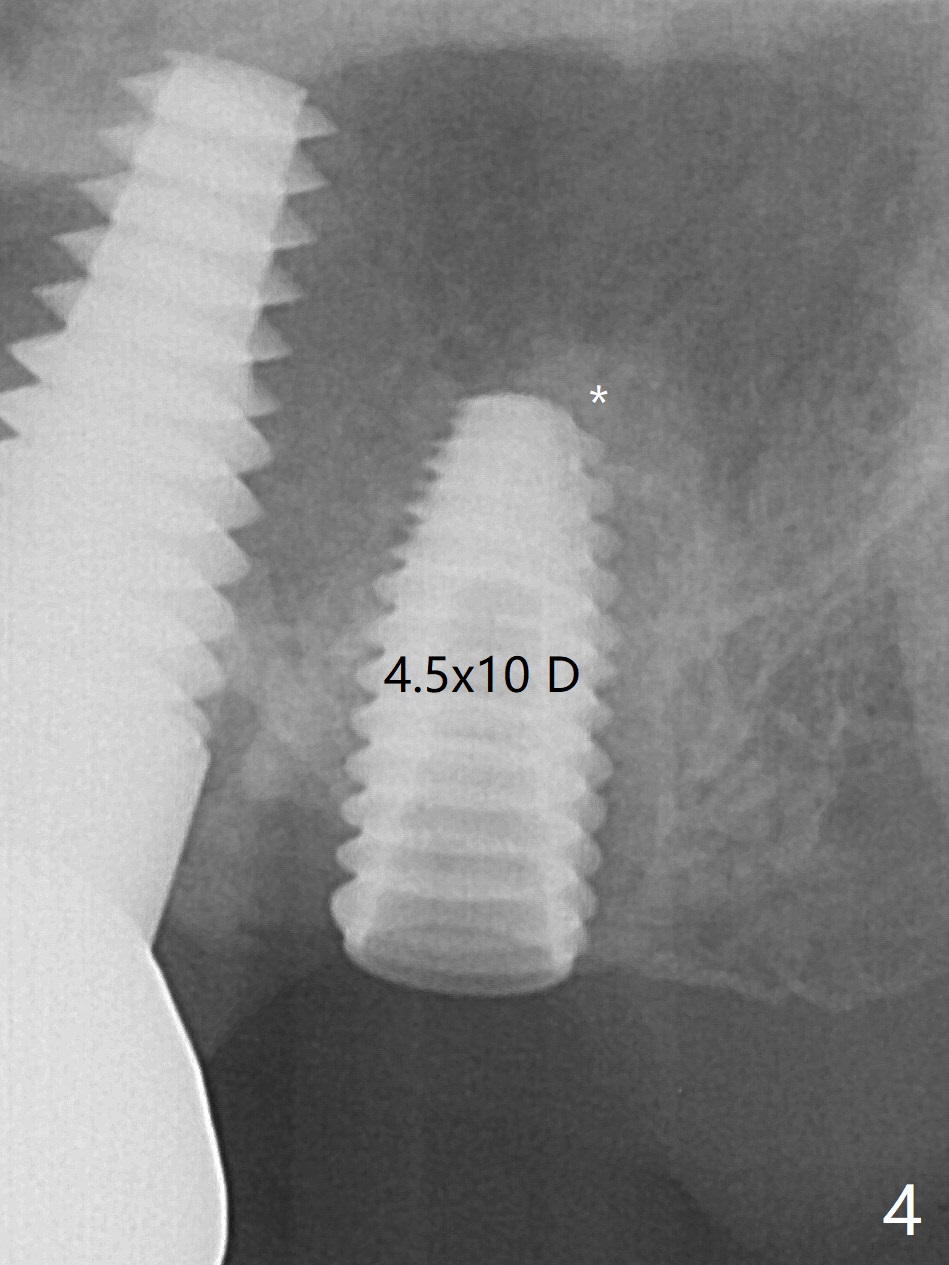

术前15号牙远中隐裂(图一:^),14号牙植体光滑面腭侧暴露(8年前腭侧窝植入),但是牙龈健康(图二)。14号牙牙槽窝没有肉芽组织,利用导板(Shinning Oral Scanner)完成3.5毫米钻洞,无法使用圆钻做内提升,改用4x10毫米报废植体提升,不幸窦膜好像破裂(因为薄),塞入半块PRF膜,促进修复,然后使用4.5x10毫米报废植体扩大植牙床(图三,四),无意达到部分提升(*),取出报废植体,发现植牙床没有穿孔了,加入少量粘性骨粉(图五:S(即使在窦内不容易分散))后,植入正式植体和基台。植体周围间隙(图五:*),使用刮匙,牙周探针,和长探针(图六)将骨粉输入深部(图七:*)。